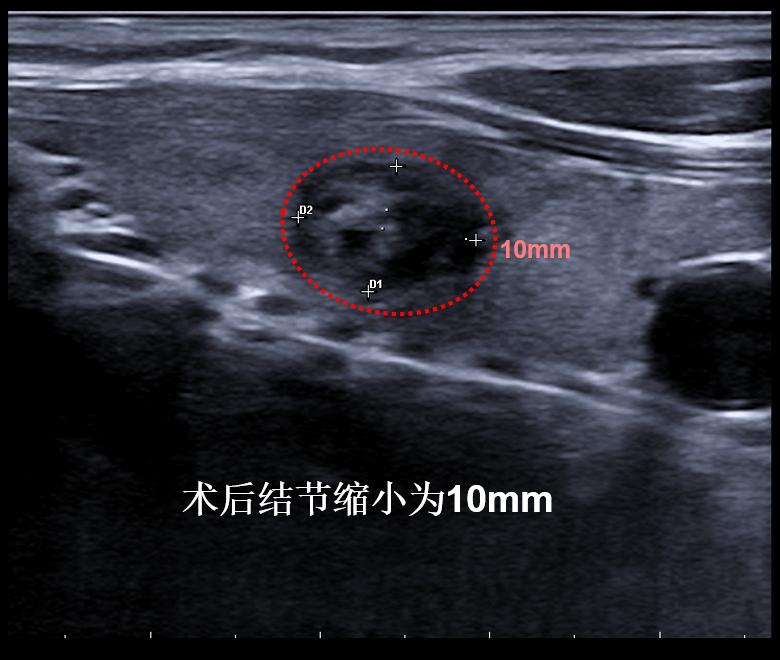

病例③: 25mm的甲状腺结节微创消融后1年半,完全吸收

微创消融前后超声对比,结节完全消失